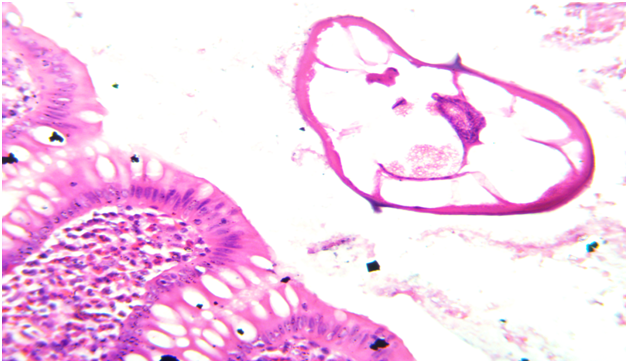

A 22 year old male patient came to the casualty department with pain in abdomen. On physical examination there was right iliac fossa tenderness. A laboratory investigation revealed a normal Complete Blood Count (CBC). Serum immunoglobulins levels were not done in this patient as clinicians did not suspect parasitic infection as a cause of acute appendicitis.Ultrasonography was performed and did not show inflammation of appendix or any other abdominal organ. Clinical diagnosis of acute appendicitis with unkown etiology was made and patient underwent open appendicectomy. The specimen was sent for histopathological examination to know the exact cause of appendicitis. On gross examination appendix appeared normal with presence of fecolith. Microscopic examination revealed mucosa with inflammatory infiltrate predominantly comprising of eosinophils which is most commonly seen in parasitic infection and lumen showed parasite of Enterobius Vermicularis (Figure 1&2). The rest of the layer submucosa, muscle layer and serosa appeared normal and showed no evidence of neutrophilic infiltrate or congested blood vessels which is usually is seen in acute appendicitis without parasitic infection. (Figure 3). The diagnosis of acute appendicitis secondary to Enterobius Vermicularis infection was given. Post operatively a dose of mebendazole 100mg was given and patient is being followed up.

Figure 2 Microscopic photo showing mucosa of appendix with eosinophils in lamina propria and enterobious vermicularis parasite in lumen. (HE, X40)